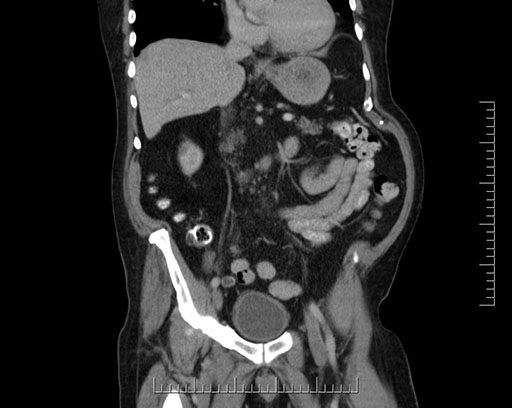

Imaging Analysis

Look through the patient's CT scan to identify any areas of concern for the necessary procedure.

Based on your CT findings, which issue(s) would give reason for "planned slowing down moment(s)" in this case?